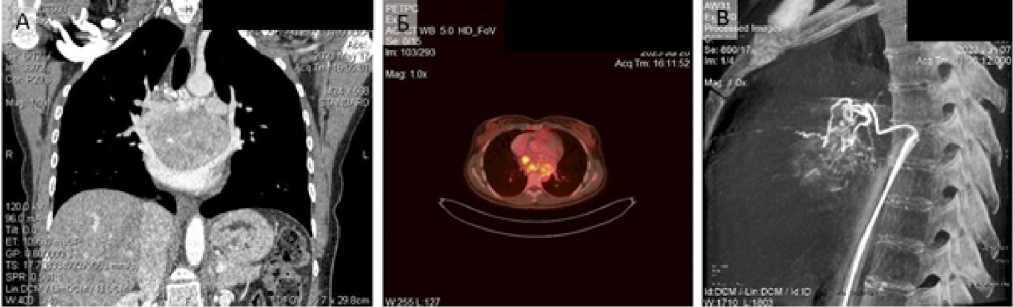

Пациентка Л., 33 года, поступила в онкологическое (торакальное) отделение УЗ «Республиканский-научно практический центр онкологии и медицинской радиологии имении Н.Н. Александрова» (далее — РНПЦ ОМР) с жалобами на повышение артериального давления (САД до 220 мм рт. ст.), давящие боли за грудиной без четкой связи с нагрузкой, ночную периодическую потливость. Из анамнеза заболевания известно, что вышеуказанные жалобы беспокоили в течение 6 мес. Специфическую гипотензивную терапию амбулаторно не принимала. В плане дообследования пациентке выполнено УЗИ сердца, по результатам которого в проекции левого предсердия определялось образование с четкими контурами, размером 84 × 49 мм, сдавливающее левое предсердие, легочные вены. Была заподозрена опухоль висцерального отдела средостения (Лимфома? Бронхогенная/энтерогенная киста?). По результатам компьютерной ангиотомографии органов грудной клетки (КТА ОГК), в заднем отделе средостения определялась опухоль с четкими ровными контурами, с накоплением контрастного вещества с 37 ед.Х до 110 ед.Х, сдавливающая легочную артерию, левое предсердие, с развитием артериальных коллатералей, общим размером 84 × 49 × 71 мм. Консилиумом рентгенологов КТ-картина была описана как опухоль заднего средостения с преимущественным интраперикардиальным распространением (рис. 1, А). Для оценки инвазии опухоли в структуры сердца пациентке была выполнена магнитно-резонансная томография (МРТ), при которой в проекции заднего отдела средостения определялось образование, размером 85 × 78 × 55 мм, с четким ровным наружным контуром, сдавливающее полость левого предсердия, уменьшая его объем. По сигнальным МР-характеристикам структура опухоли изоинтенсивна мышечной ткани.

Рис. 1. Результаты рентгенологических методов исследования: А — КТА-ОГК; Б — ФДГ ПЭТ-КТ; В — Селективная ангиография

Fig. 1. Results of radiological evaluation: A — chest CTA; Б — FDG-PET-CT; B — selective angiography

Для дифференциальной диагностики с лимфопролиферативными заболеваниями, а также для уточнения распространенности опухолевого процесса была выполнена позитронно-эмиссионная томография с фтордезоксиглюкозой (ФДГ ПЭТ-КТ) (рис. 1, Б), по результатам которой в висцеральном отделе средостения определялось гетерогенное солидное образование с четкими контурами, размером до 80 × 53 × 70 мм, содержащее в структуре единичные линейные сосуды. Опухоль диффузно и неравномерно накапливала радиофармпрепарат (SUVmax 2,7-6,1).

При ангиографии установлен источник кровоснабжения опухоли: ветви левой бронхиальной артерии (рис. 1, В). Однако селективная установка микрокатетера оказалась невозможной в связи с выраженной извитостью ветвей бронхиальной артерии, что сделало проведение безопасной эмболизации невозможной.